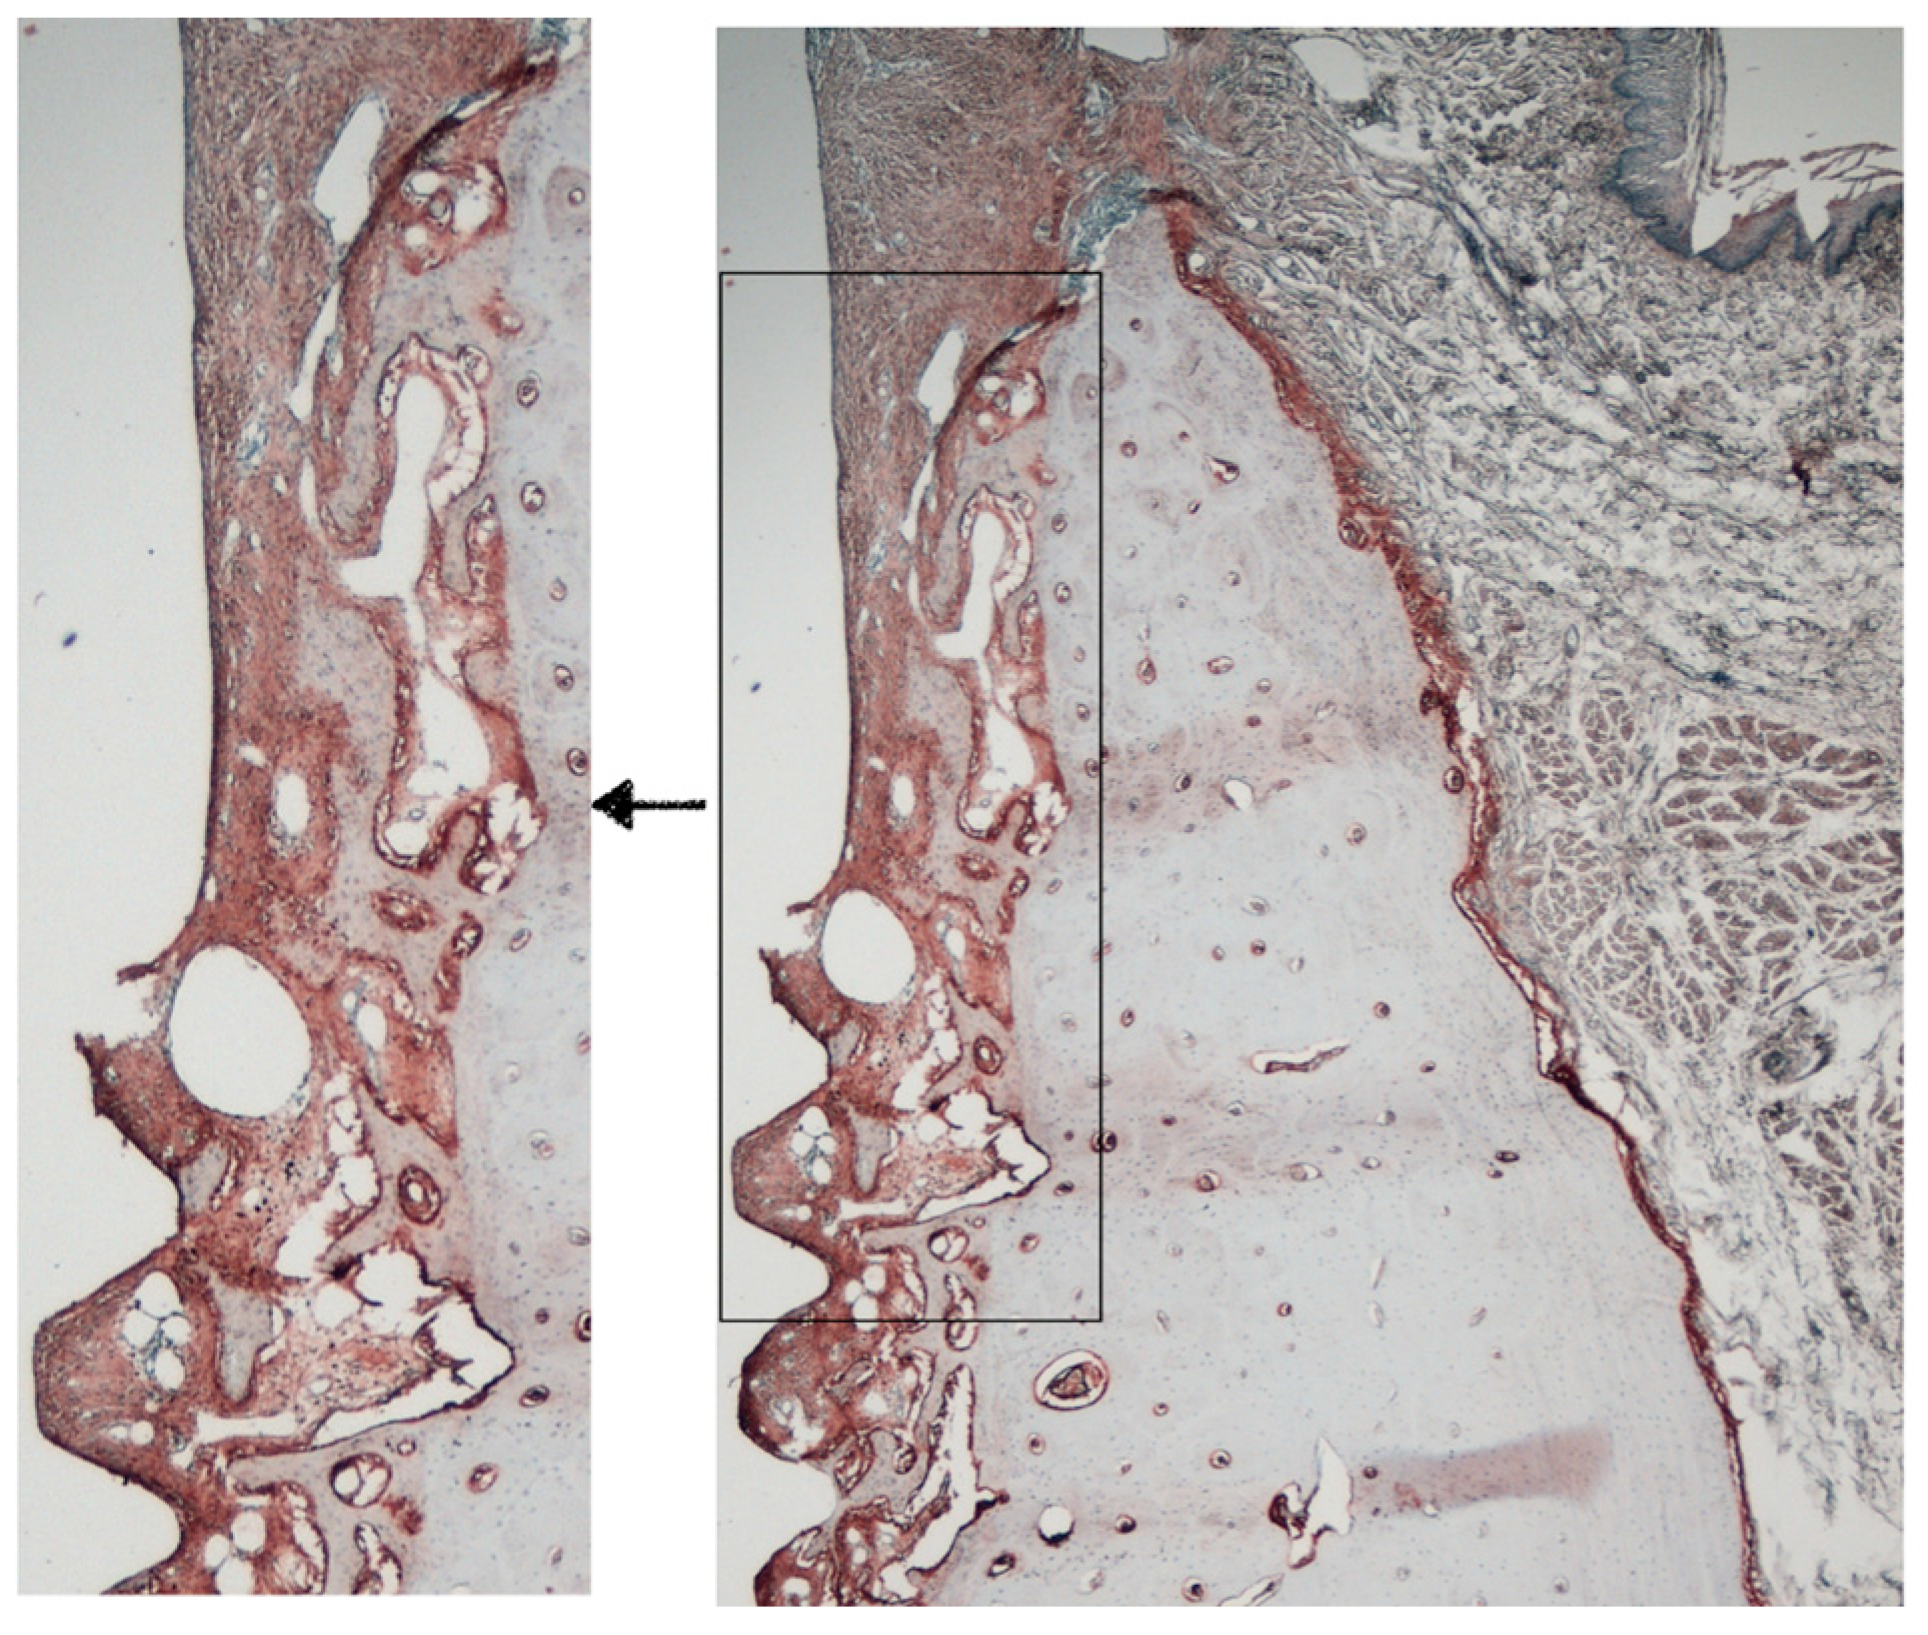

3.2. Histology and Histomorphometry

3.3. Histometric Results